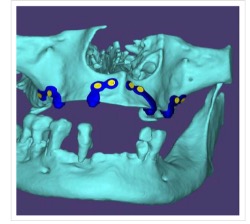

- CBCT-based 3D reconstruction

- CAD-based virtual implant design

- Finite Element Analysis (FEA) for stress distribution assessment

- Passive adaptation of custom subperiosteal implant framework

- Fixation using titanium screws (multiple anchorage points)